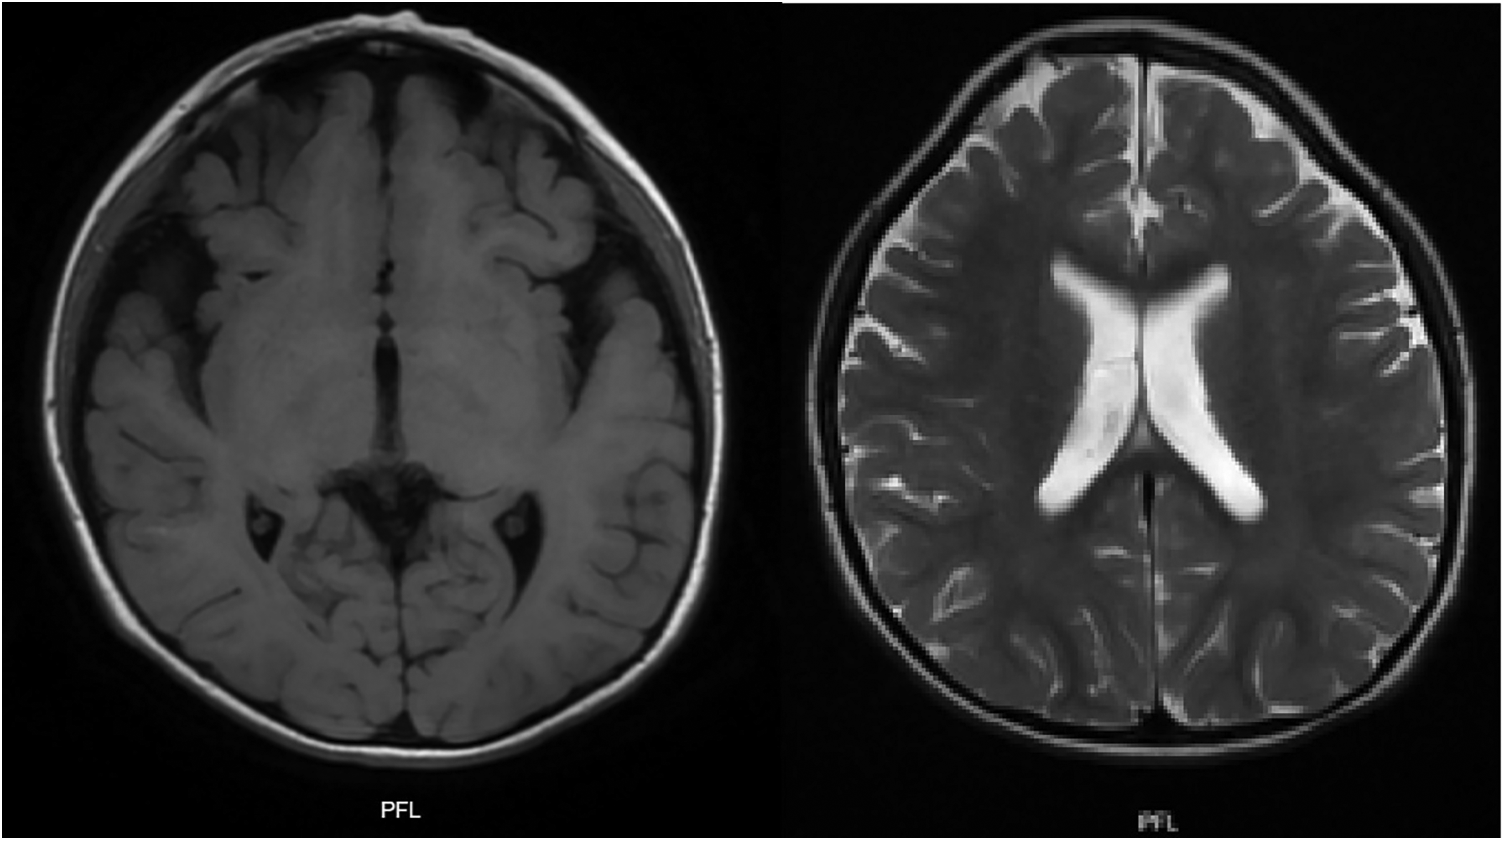

The multi-systemic nature of her symptoms and the need for diverse specialist evaluations elongated the diagnostic journey. By the age of four, persistent neurodevelopmental delays were accompanied by constipation and feeding difficulties. Additional advanced investigations were conducted to pinpoint a diagnosis. Brain magnetic resonance imaging (MRI) disclosed progressive abnormalities involving the frontal lobes, as well as an expanded subarachnoid space and ventricular system (Figure 3). Esophageal manometry verified swallowing disorders, while polysomnography identified obstructive hypopneas, resulting in a diagnosis of moderate obstructive sleep apnea-hypopnea syndrome (OSAHS) (apnea-hypopnea index of 11.9); this was managed with continuous positive airway pressure (CPAP) therapy. Table 1 chronologically summarizes the analysis performed on the patient.

Figure 3

T1 and T2 weighted brain MRI: plagiocephaly, cortical atrophy, involvement of the white matter and frontal lobes is observed. Generalized increase in the amplitude of the subarachnoid space and ventricular system.

In terms of neuroimaging findings, microdeletions at the 5q31.3 locus are known to impact the brain, affecting both white matter and the frontal lobes (22). Initially, these alterations are latent but progress over time to result in volume loss, delayed myelination, and demyelination. In line with this, the patient's initial brain MRI displayed a reduction in the frontal lobe volume, a finding corroborated by similar cases (23, 24).